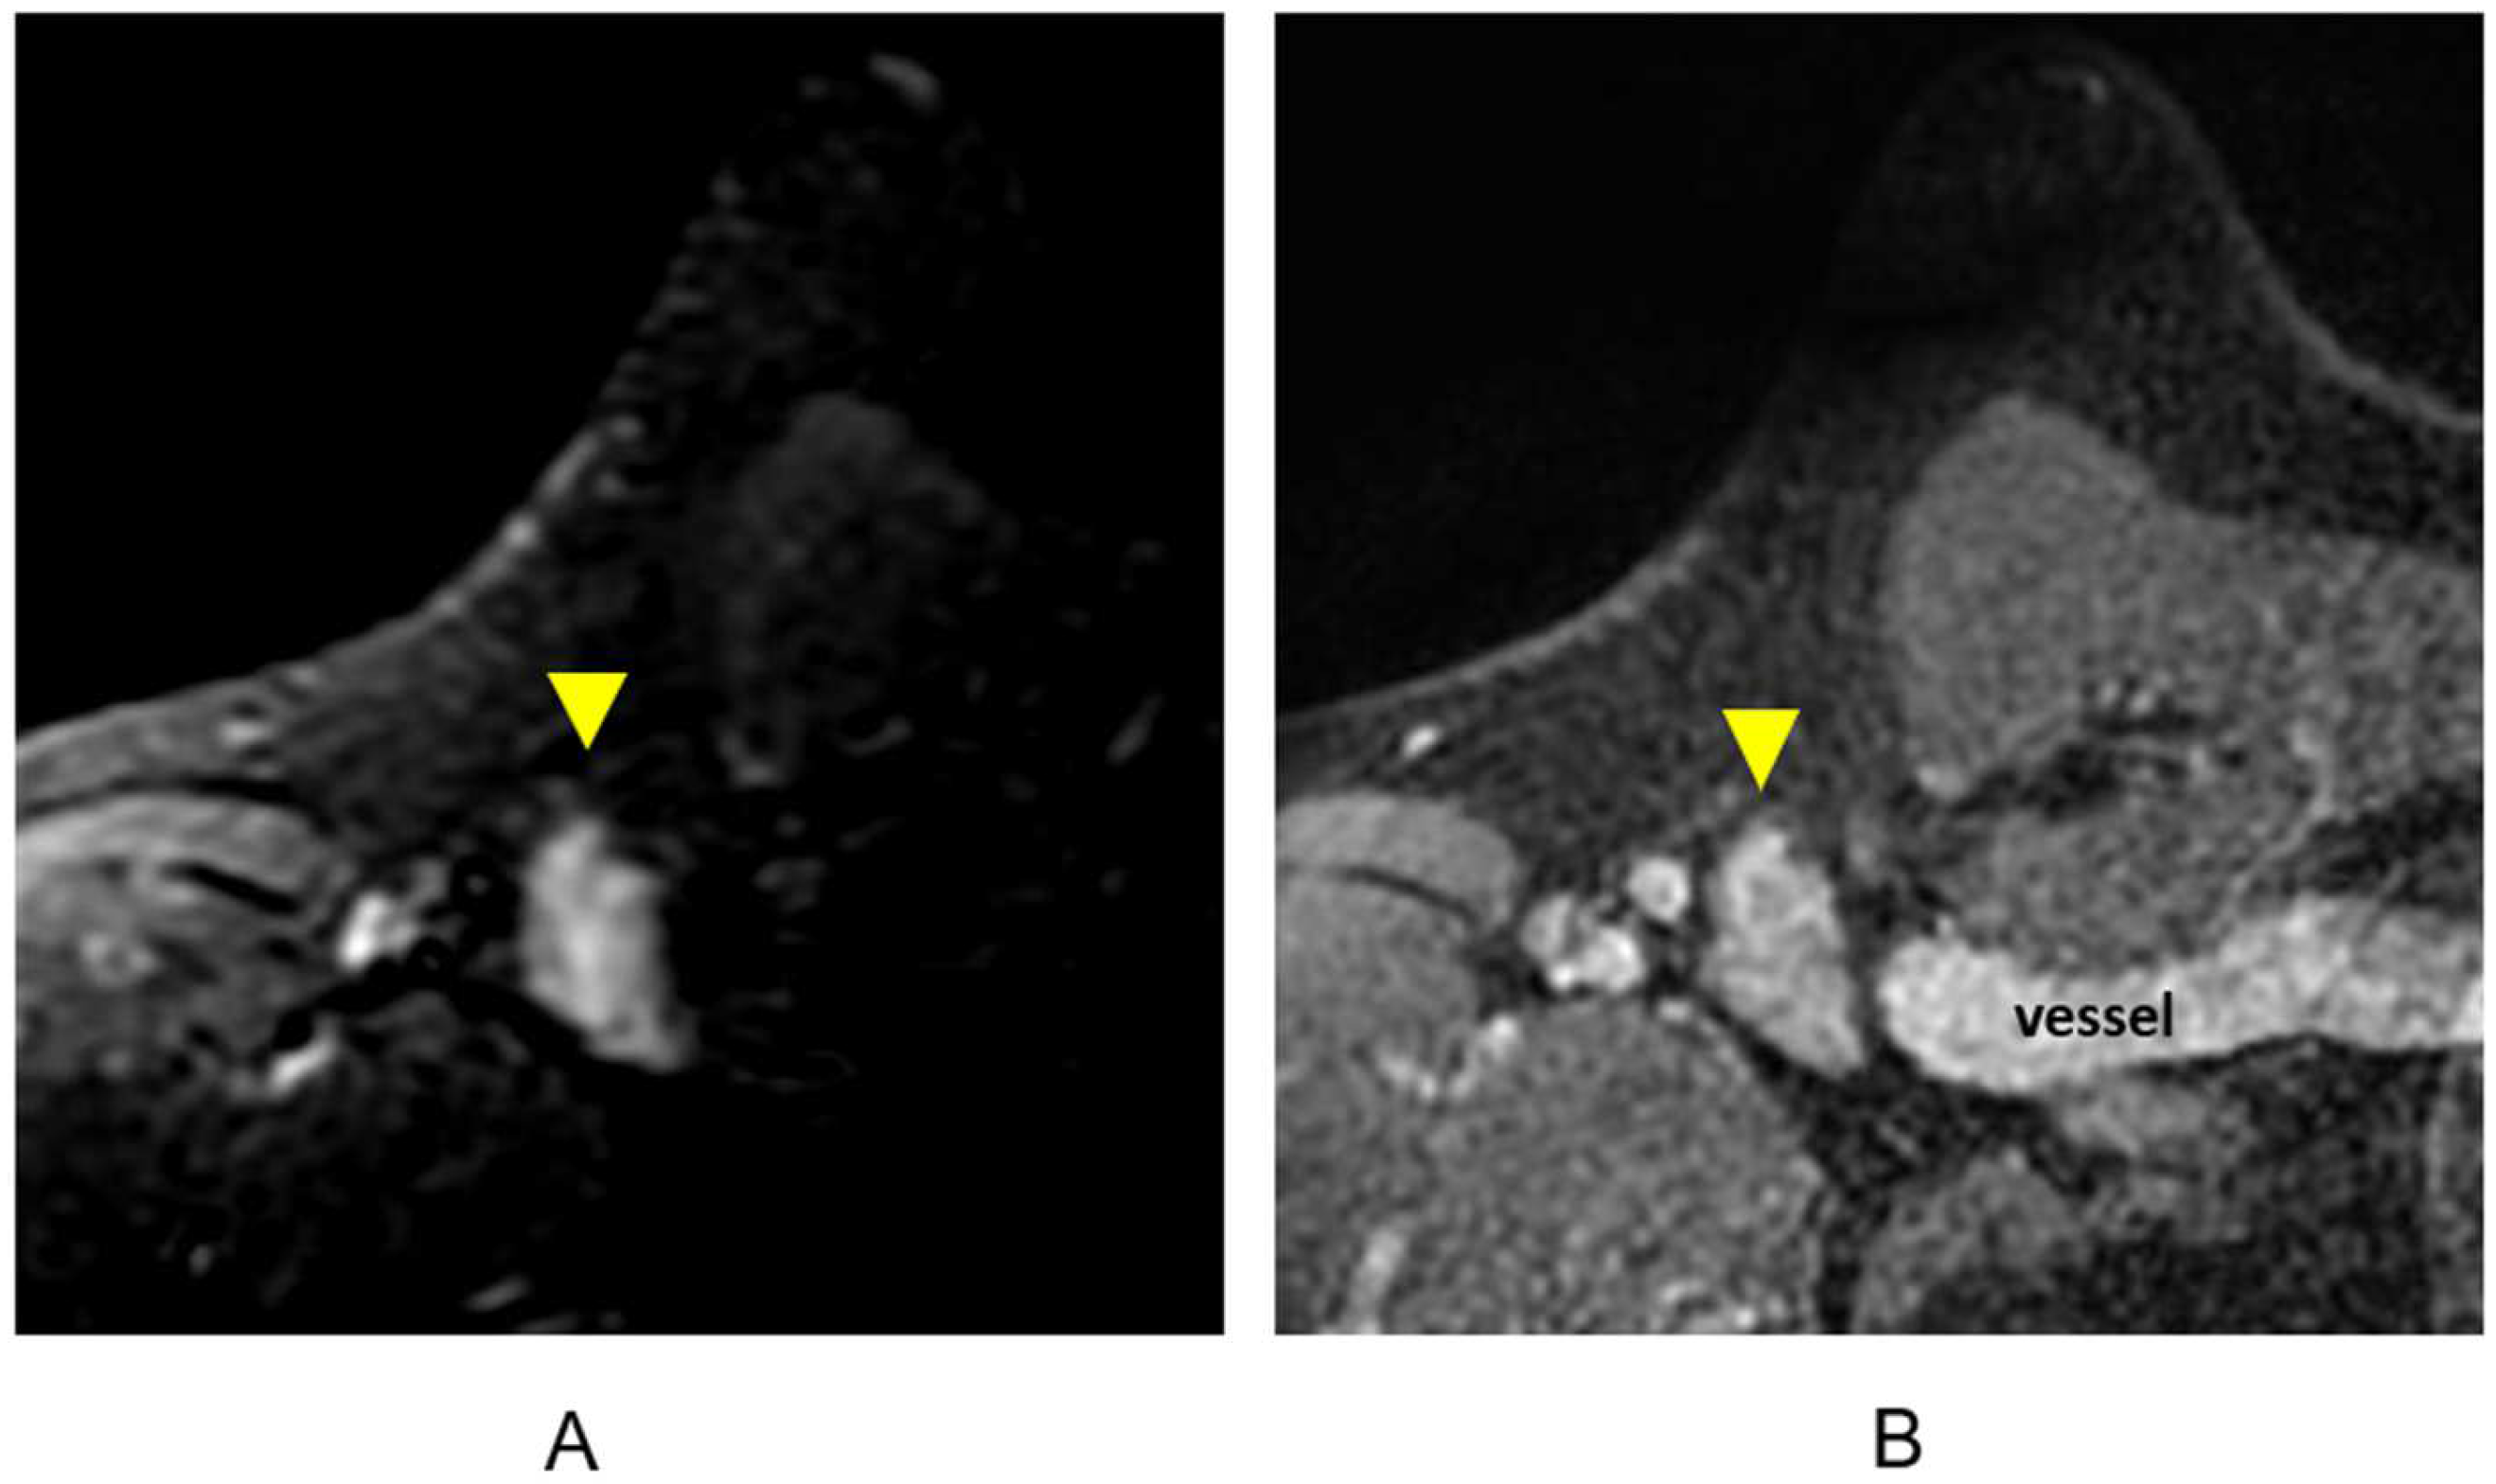

3.1.6. Evaluation of Internal Mammary Lymph Nodes (IMLNs)